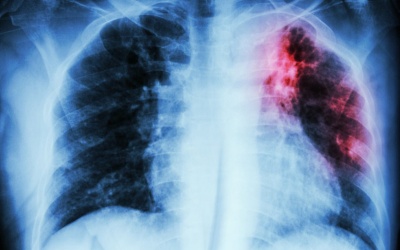

Các nhà khoa học Trung Quốc vừa tìm ra một loại gene "chủ chốt" có thể mở ra nhiều hy vọng phát triển hướng điều trị mới cho các bệnh nhân mắc bệnh ung thư phổi, một trong những loại...